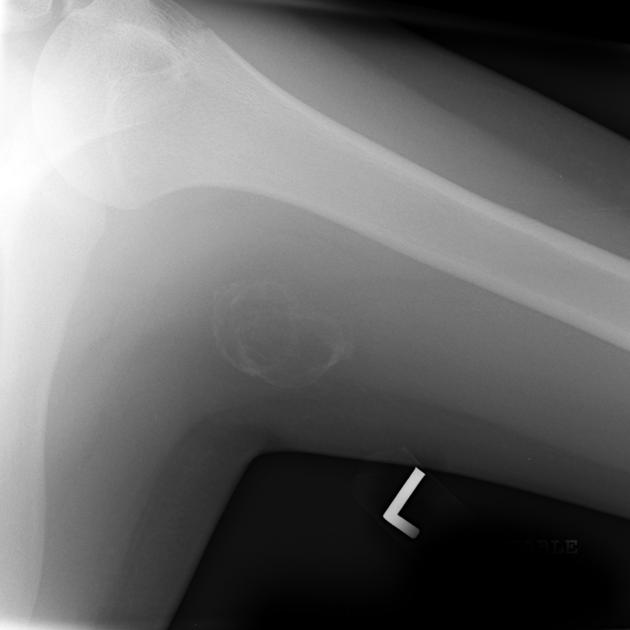

Figure 1 demonstrates early calcification of a myositis ossificans lesion in the left triceps muscle. As is characteristic, there is an outer shell of bone with a lucent central region. Figure 2 is a more mature, well-defined lesion with a dense periphery at the medial aspect adjacent to the femur.

Radiographically, findings may appear as early as 3 to 4 weeks post-injury. Initially, there may be a hazy increase in density in the soft tissues. With time, the bone formation will be noted at the periphery of the lesion, forming a shell. Progressive ossification of the lesion may follow, characteristically with a denser periphery and a relatively lucent central region. The lesion is usually mature at 2-6 months. Typically, a radiolucent cleft is seen separating the lesion from the underlying bone. After reaching maturity, the lesion usually will regress in size. This appearance is a key to differentiating myositis ossificans from parosteal osteosarcoma, which is the main differential diagnosis. These soft tissue sarcomas tend to have greater density at the center of the lesion and a less dense periphery. Lesion biopsy is not a reliable differentiator between sarcoma and MO, as histologically the two may be very similar, and, thus, an MO lesion should not be biopsied.